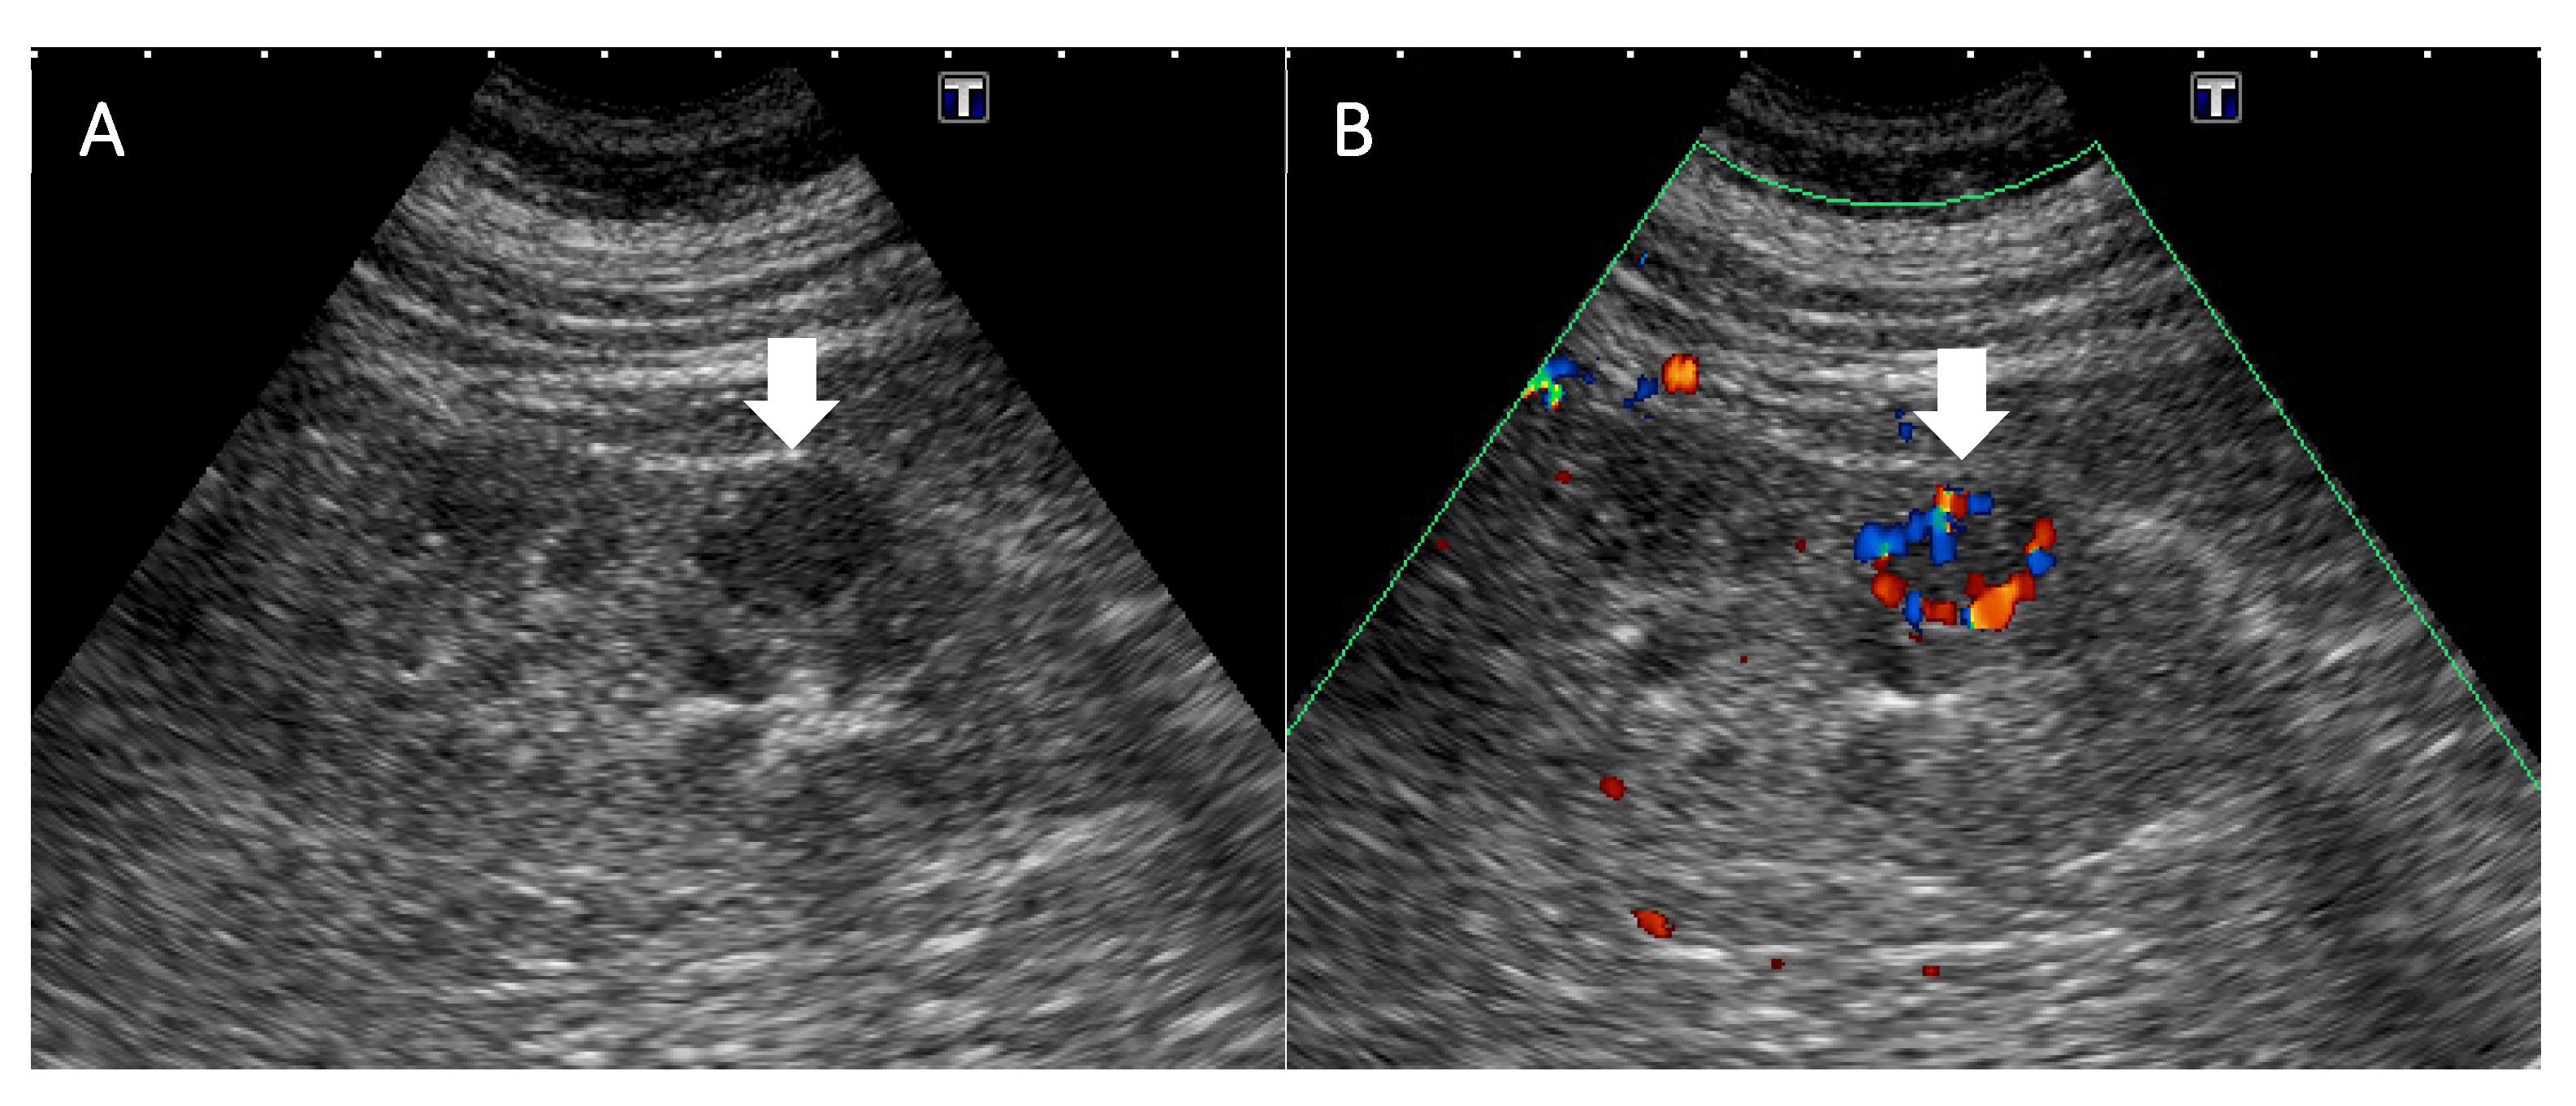

| 8 | 56/F | None Incidentally found | ESRD, HTN, diabetes, hyperlipidemia | Right lateroposterior cortex of the lower pole | 1.3 cm | US: Lesion detected MRI: Iso-intensity in the T1- and T2-weighted images and low ADC value CT: Early enhancement, suspecting RCC | HV | Laparoscopic nephroureterectomy | Free of disease 17 months after surgery | Our case |